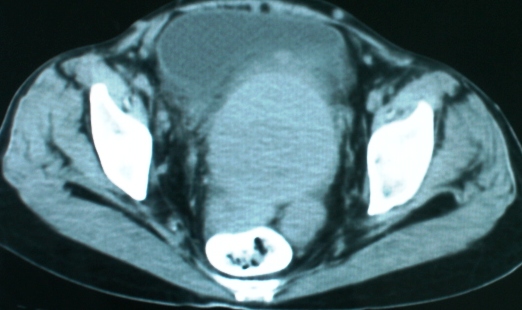

以下是引用zsl6918在2008-11-4 19:14:00的发言:[br]多发转移性改变,子宫改变不除外为原发灶